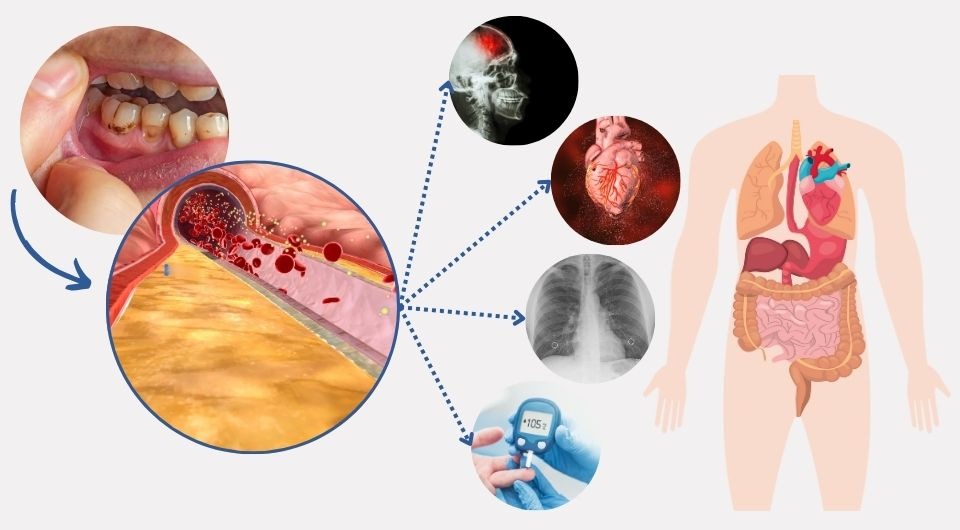

بیماری لثه و ارتباط آن با بیماری های سیستمیک، یکی از شایعترین بیماریهای مزمن در جهان بیماری لثه و التهاب...

سلامت لثهها یکی از ارکان اصلی حفظ بهداشت دهان و دندان است. لثههای سالم نه تنها به زیبایی دندانها کمک...